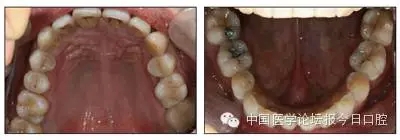

全口曲面體層片(圖3)顯示,患者全牙列牙槽骨吸收;根尖片(圖4)示11近中牙槽骨角形吸收已達根尖1/3,21牙槽骨嵴頂吸收至根1/2,23牙槽骨近中骨板角形吸收至根1/2。磨牙區(qū)骨嵴頂吸收3mm。治療前頭顱側位片見圖3,治療前ODS模型見圖5。

圖5 治療前ODS模型